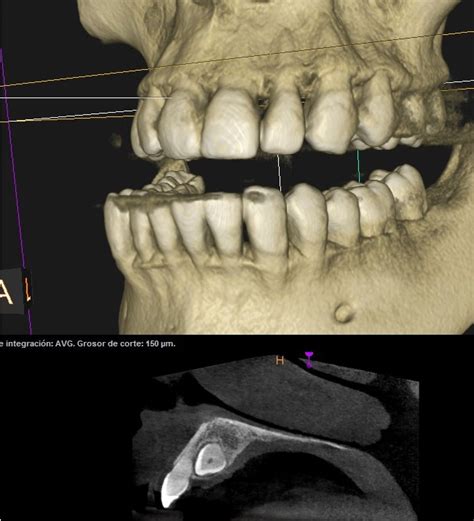

Un TAC dental es una prueba diagnóstica que utiliza rayos X para obtener imágenes tridimensionales (3D) de los dientes, maxilares y estructuras circundantes. A diferencia de las radiografías convencionales, que ofrecen imágenes en 2D, el TAC dental proporciona una visión más completa y detallada de la anatomía dental y ósea del paciente.

El TAC bucal sirve para hacer un completo estudio radiológico de la boca del paciente, ya que permite obtener imágenes de sus estructuras dentales y óseas. El TAC dental sirve para tomar imágenes tridimensionales de las estructuras nerviosas, los dientes y los huesos craneofaciales, es una prueba diagnóstica.

Cuando las radiografías dentales o faciales no son suficientes, se realiza el TAC dental. El TAC dental capta centenares de imágenes de todas las estructuras anatómicas de la boca: músculos, huesos, vasos sanguíneos y nervios.

Planeacion de un Implante Dental